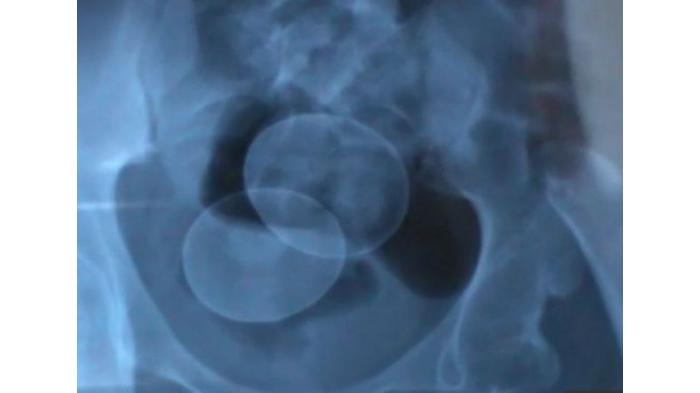

Dokter mengklaim, dua butir telur tersebut adalah telur ayam ras secara fisik dan berada di dalam tubuh Akmal secara sengaja.

"Jika bicara tentang disiplin ilmu, telur tersebut sengaja dimasukkan melalui anus dan cara memasukkannya adalah wewenang polisi untuk mengungkapnya," kata dr Ratnah Latief.

Saat itu, telur yang keluar dari tubuh Akmal adalah telur ayam kampung sesuai dengan uji laboratorium forensik.